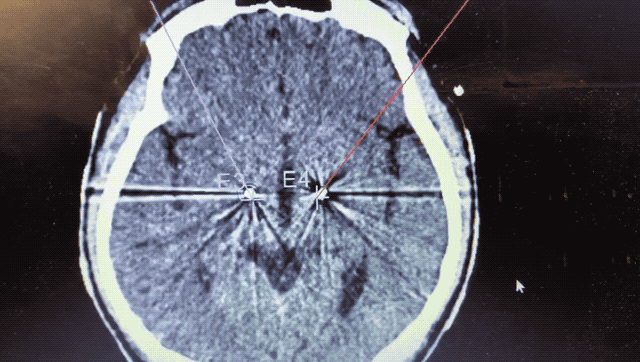

順利檢測到典型的核團(tuán)信號后,再次植入刺激電極到相應(yīng)位置,測試后即可完成單側(cè)的電極植入。對側(cè)只需借助機(jī)器人再次定位,并將檢測電極、刺激電極依次植入,最后,還需將刺激器植入患者胸前皮下。根據(jù)術(shù)后CT顯示,本手術(shù)雙側(cè)植入電極的位置與術(shù)前規(guī)劃路徑完全吻合,患者開機(jī)后,起搏器會開始沿刺激電極向患者核團(tuán)實施高頻電刺激,以減輕疾病癥狀,提高患者的生活質(zhì)量。

術(shù)后CT顯示雙側(cè)電極植入位置與規(guī)劃完全吻合